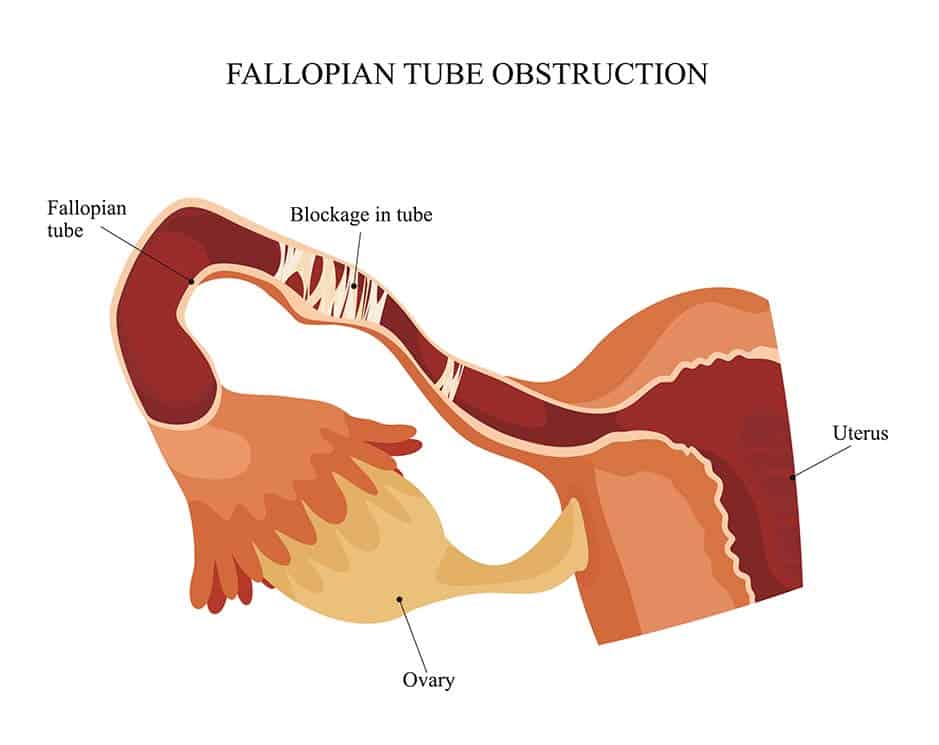

Tubal Blockage Causes Symptoms Treatments Our Approach

Fallopian Tube Blockage

Fallopian Tube Blockage

Blocked Fallopian Tubes Causes Symptoms And Treatment

Blocked Fallopian Tubes Symptoms Causes And Treatment